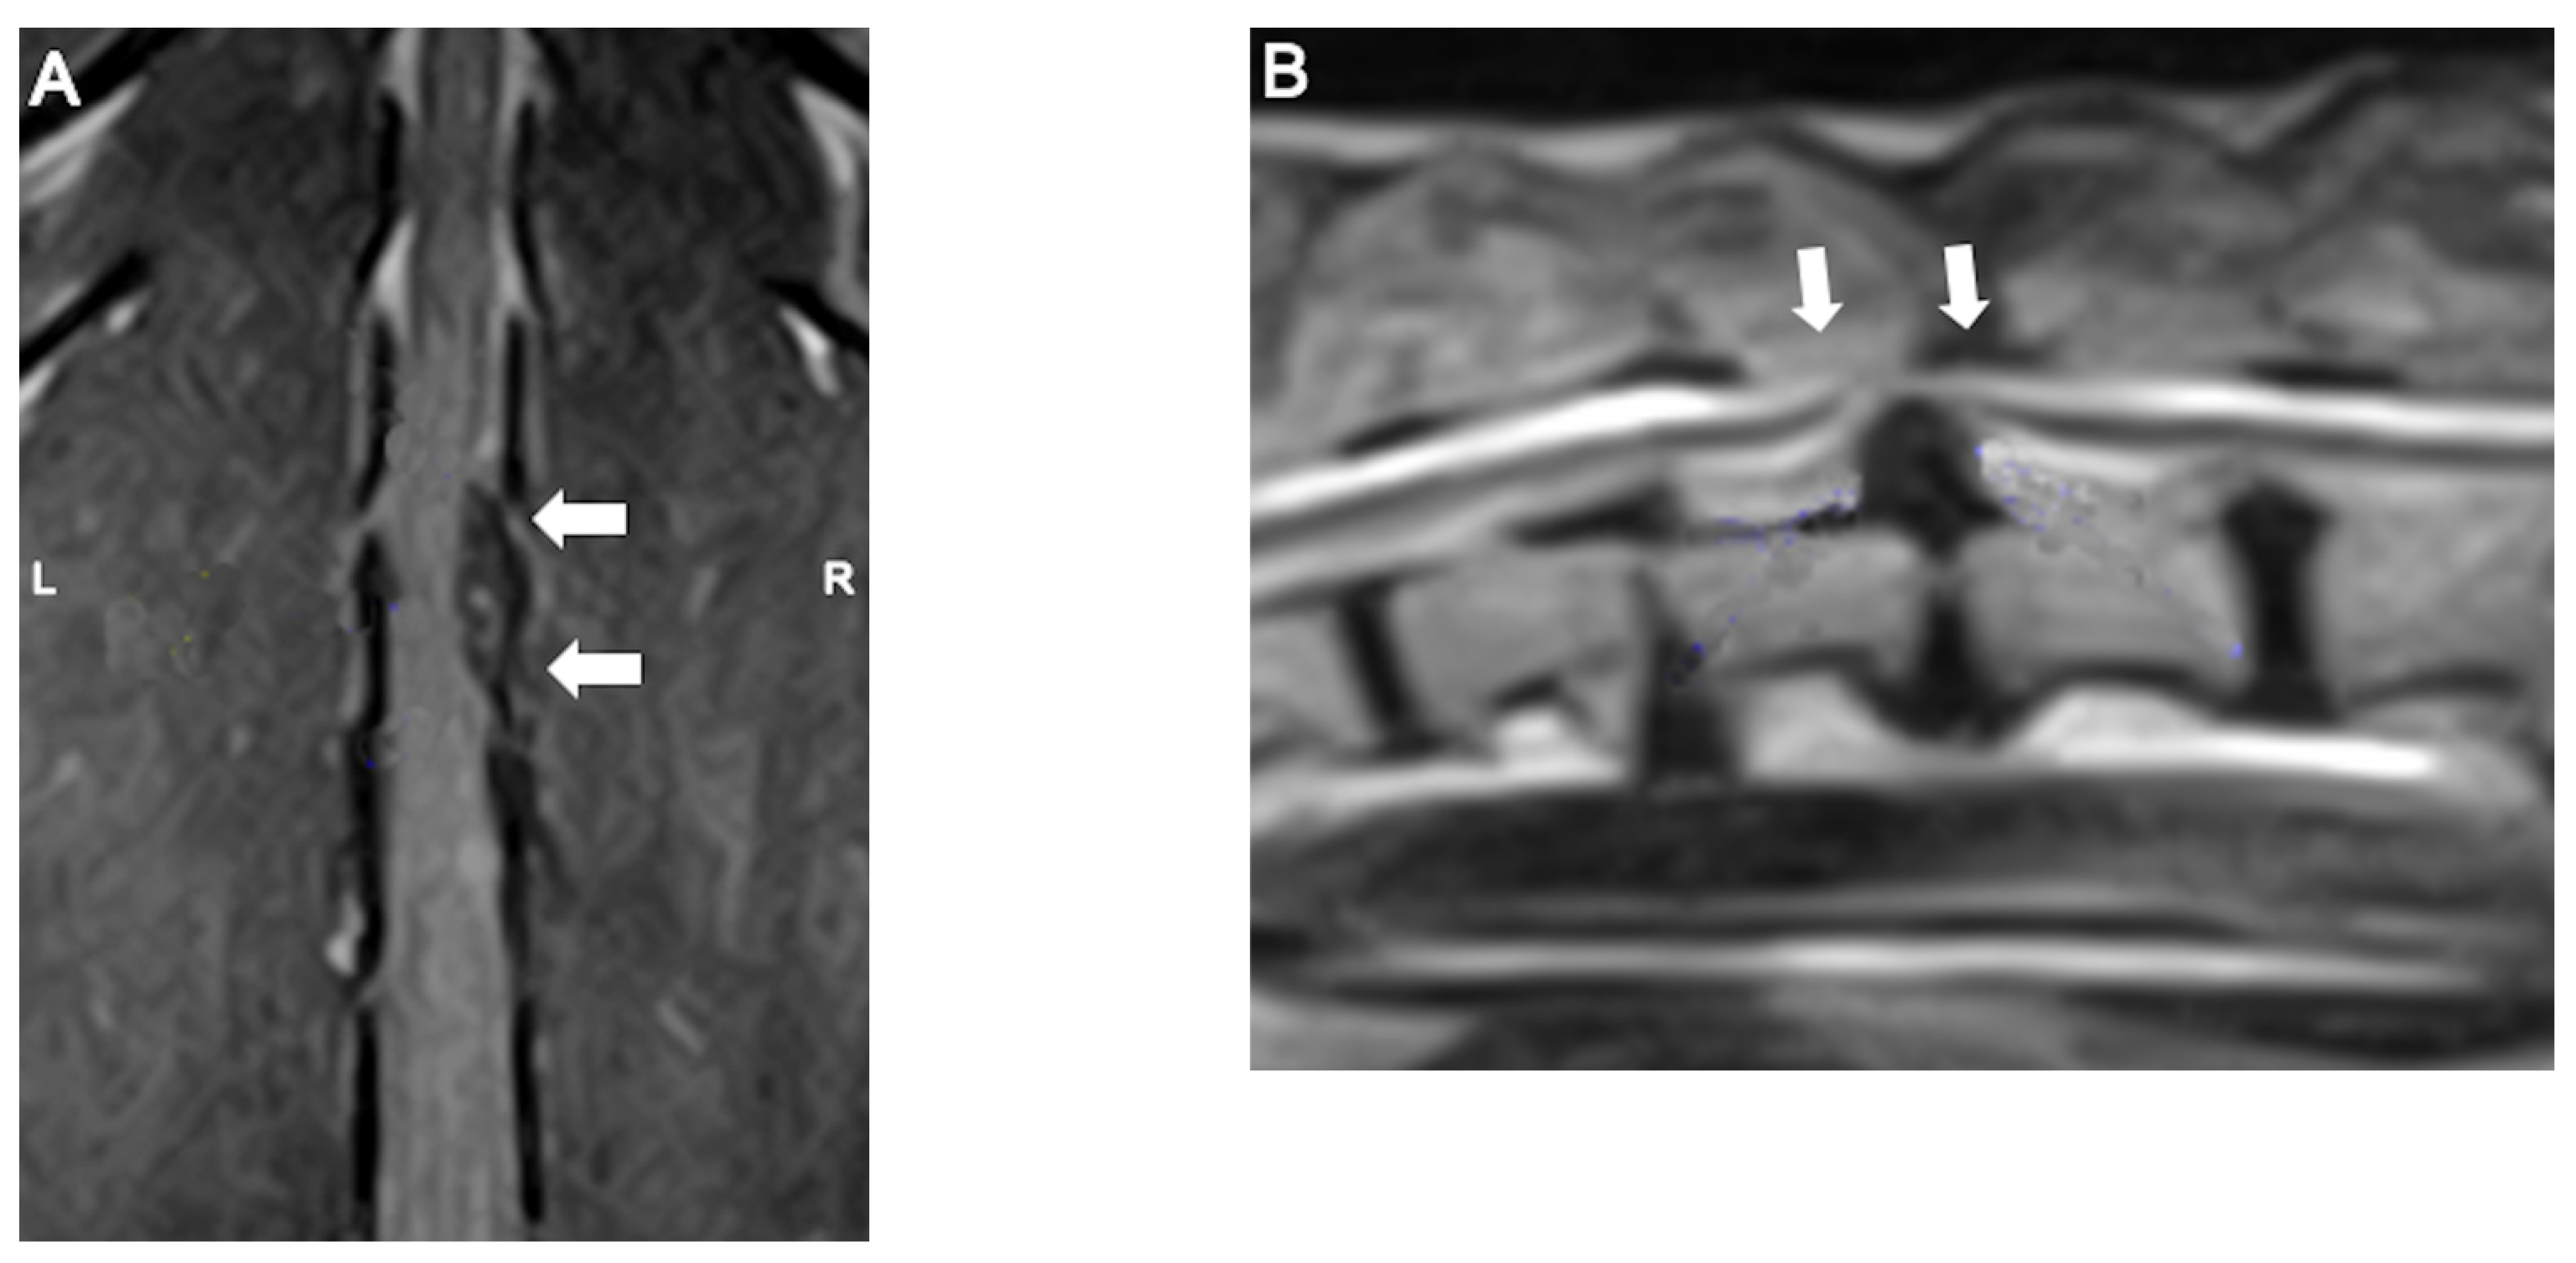

- da Costa, R. C., De Decker, S., Lewis, M. J., Volk, H., & Canine Spinal Cord Injury Consortium (CANSORT-SCI). (2020). Diagnostic Imaging in Intervertebral Disc Disease. Frontiers in Veterinary Science, 7, 588338. [CrossRef]

- Robertson, I., & Thrall, D. E. (2011). Imaging dogs with suspected disc herniation: Pros and cons of myelography, computed tomography, and magnetic resonance. Veterinary Radiology & Ultrasound: The Official Journal of the American College of Veterinary Radiology and the International Veterinary Radiology Association, 52(1 Suppl 1), S81-84. [CrossRef]

- Noyes, J. A., Thomovsky, S. A., Chen, A. V., Owen, T. J., Fransson, B. A., Carbonneau, K. J., & Matthew, S. M. (2017). Magnetic resonance imaging versus computed tomography to plan hemilaminectomies in chondrodystrophic dogs with intervertebral disc extrusion. Veterinary Surgery: VS, 46(7), 1025–1031. [CrossRef]

- Cooper, J. J., Young, B. D., Griffin, J. F., Fosgate, G. T., & Levine, J. M. (2014). Comparison between noncontrast computed tomography and magnetic resonance imaging for detection and characterization of thoracolumbar myelopathy caused by intervertebral disk herniation in dogs. Veterinary Radiology & Ultrasound: The Official Journal of the American College of Veterinary Radiology and the International Veterinary Radiology Association, 55(2), 182–189. [CrossRef]

- Wang-Leandro, A., Siedenburg, J. S., Hobert, M. K., Dziallas, P., Rohn, K., Stein, V. M., & Tipold, A. (2017). Comparison of Preoperative Quantitative Magnetic Resonance Imaging and Clinical Assessment of Deep Pain Perception as Prognostic Tools for Early Recovery of Motor Function in Paraplegic Dogs with Intervertebral Disk Herniations. Journal of Veterinary Internal Medicine, 31(3), 842–848. [CrossRef]